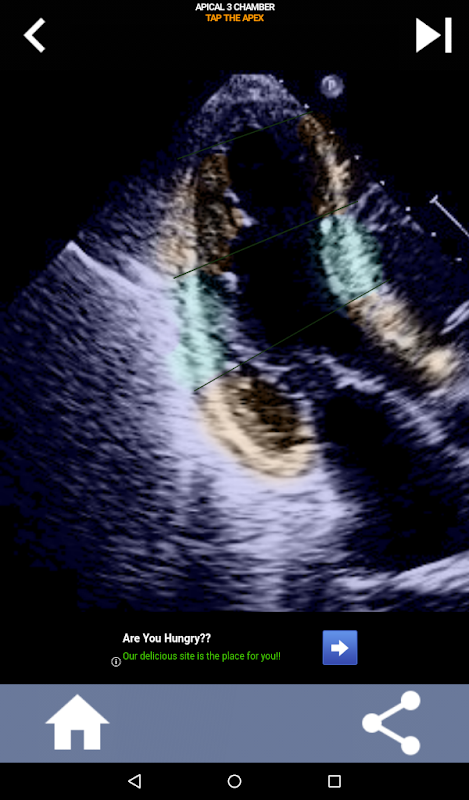

AHA kalp segmentlerini öğrenmek için sınava dayalı görsel yaklaşım: Ekokardiyografi

Bu uygulama, genellikle en iyi öğretim yöntemi olarak bulduğum gerçek yankı görüntülerini kullanarak bilginizi test edecek.